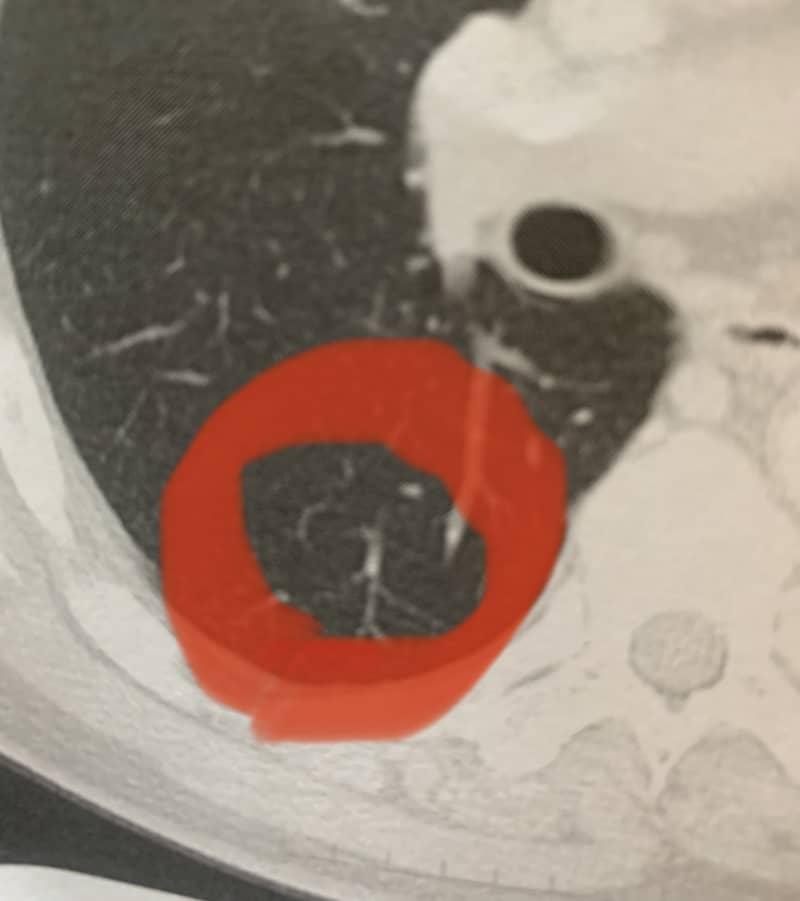

転移の肺癌が消えた。抗がん剤7回目

抗がん剤のFOLFIRINOX療法6回目でCTを撮りました。

本日、結果について主治医から説明があり、肺に転移した癌が画面上からすべて消えて、癌が消滅したとの診断でした。

再発した時は膵臓癌からの肺転移でステージ4で余命1年くらいと診断された訳ですが、今日は1年間この抗がん剤を続けて、そこから、抗がん剤を調整していきましょうと言われ。

先生もこんなに抗がん剤治療が効いているのを見たことが無いと言われました。